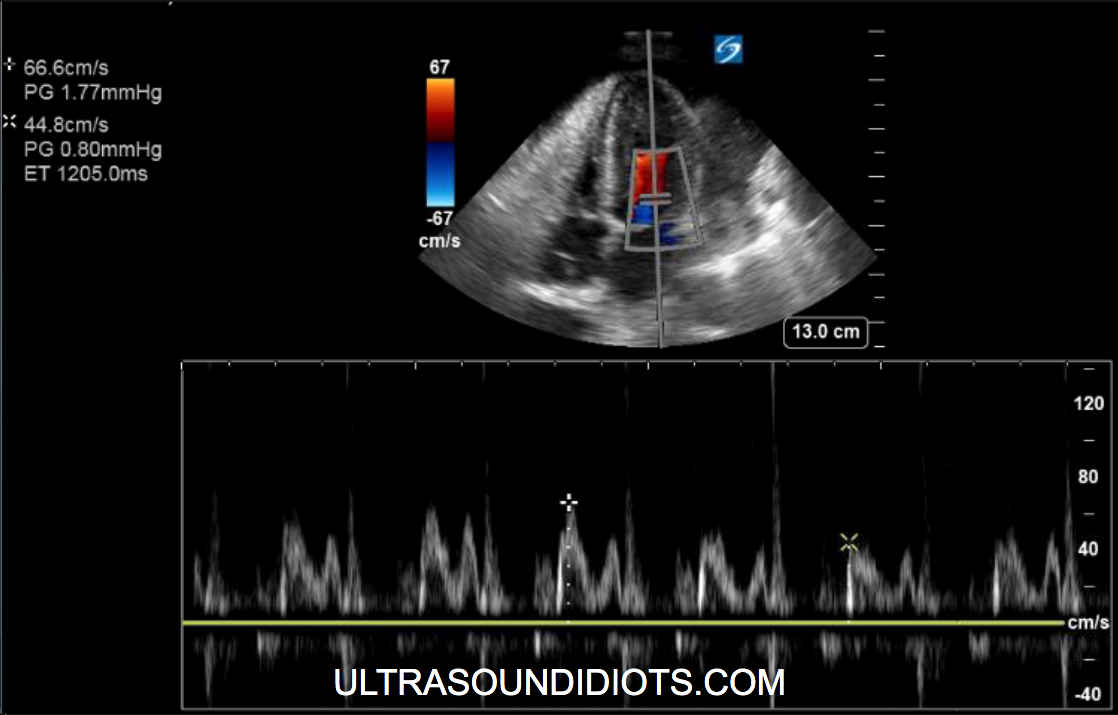

Pulsus Paradoxus by echo (Fig 1f)

DIlated IVC (fig 1g)